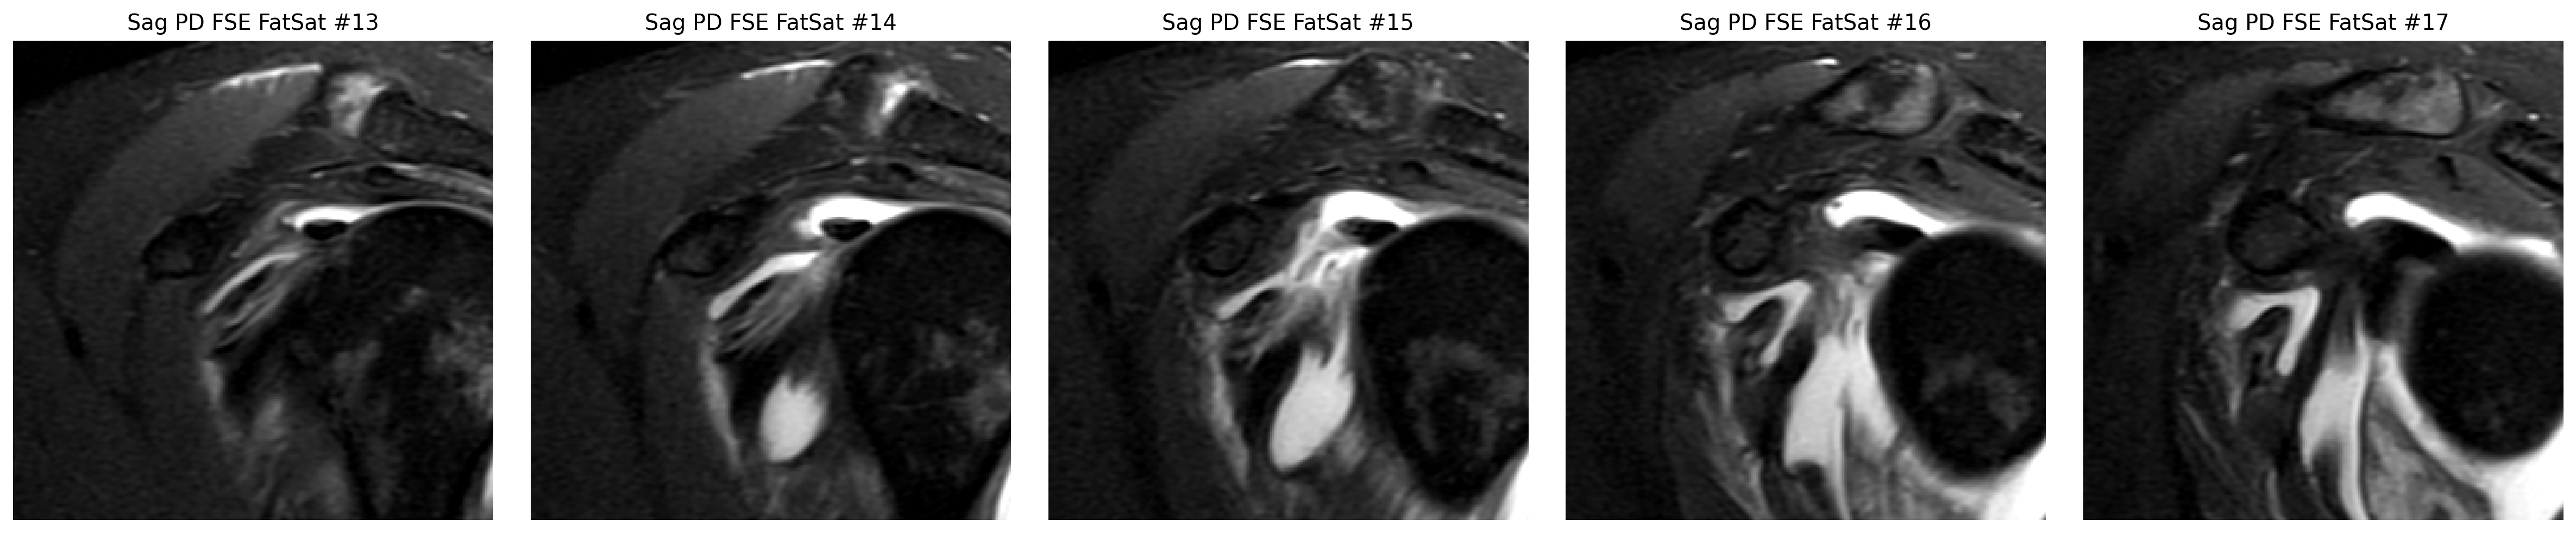

Step 2

The cuff finding was checked in coronal and sagittal views, while the labrum was reviewed on axial arthrogram slices.

The strongest image-only read is a smaller tear or split on the joint-facing side of the supraspinatus tendon where it attaches to bone.

Nearby bursal irritation or bursitis